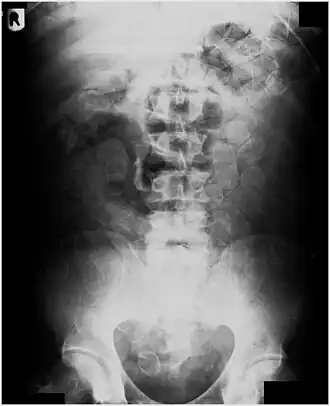

Abdominal X-ray showing small packages of cocaine swallowed by a trafficker.